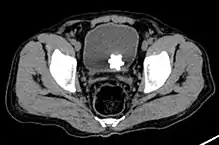

The diagnosis of bladder stone includes urinalysis, ultrasonography, x rays or cystoscopy (inserting a small thin camera into the urethra and viewing the bladder). The intravenous pyelogram can also be used to assess the presence of kidney stones. This test involves injecting a radiocontrast agent which is passed into the urinary system. X-ray images are then obtained every few minutes to determine if there is any obstruction to the contrast as it is excreted into the bladder. Today, intravenous pyelogram has been replaced at many health centers by CT scans. CT scans are more sensitive and can identify very small stones not seen by other tests.[8]

Jackstone calculus

Jackstone calculi are rare bladder stones that have an appearance resembling toy jacks. They are almost always composed of calcium oxalate dihydrate and consist of a dense central core and radiating spicules. They are typically light brown with dark patches and are usually formed in the urinary bladder and rarely in the upper urinary tract. Their appearance on plain radiographs and computed tomography in human patients is usually easily recognizable. Jackstones often must be removed via cystolithotomy.[10]